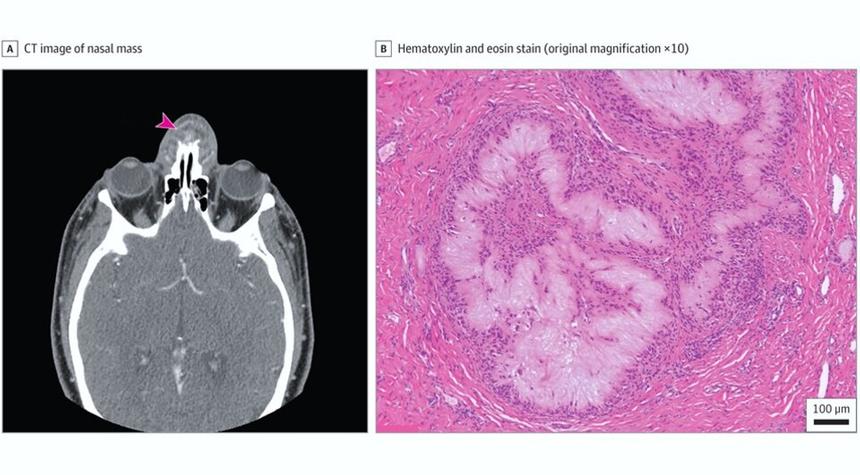

Проведённая компьютерная томография (КТ) «выявила скопление жидкости в мягких тканях вдоль переднего края носовых костей, которое вызвало эрозию костей». Осмотр полости носа с последующим дренированием выявил белые творожистые выделения. В процессе назначенной антибиотикотерапии пациент снова обратился за помощью, так как характерные для подагры покраснения снова проявились в области переносицы. Специалисты заподозрили абсцесс носа и направили пациента на операцию.

«Во время операции хирурги отметили, что новообразование имеет капсулу и прикреплено к костно-хрящевому соединению со значительным рубцеванием и перестройкой кости. На разрезе образование имело белую творожистую структуру. Гистологический анализ показал изъязвлённый плоский эпителий с признаками острого и хронического воспаления. Нижележащие мягкие ткани и кости содержали многочисленные скопления бледного эозинофильного, аморфного или фибриллярного материала, который был окружён частоколом гистиоцитов и многоядерных гигантских клеток», — цитирует медиков портал N+1.